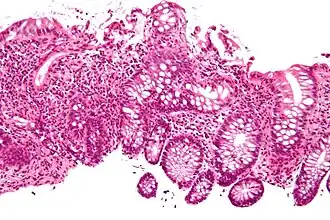

-

Crypt abscess. H&E stain.